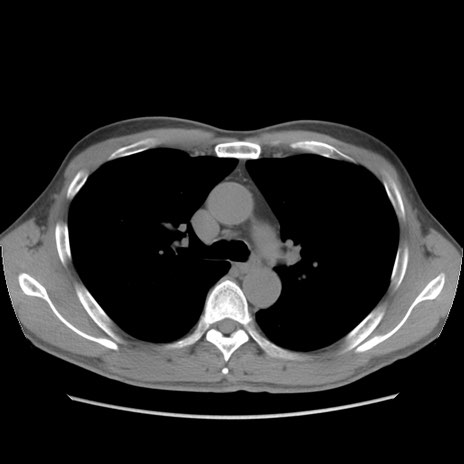

症例56 CT(横断像)